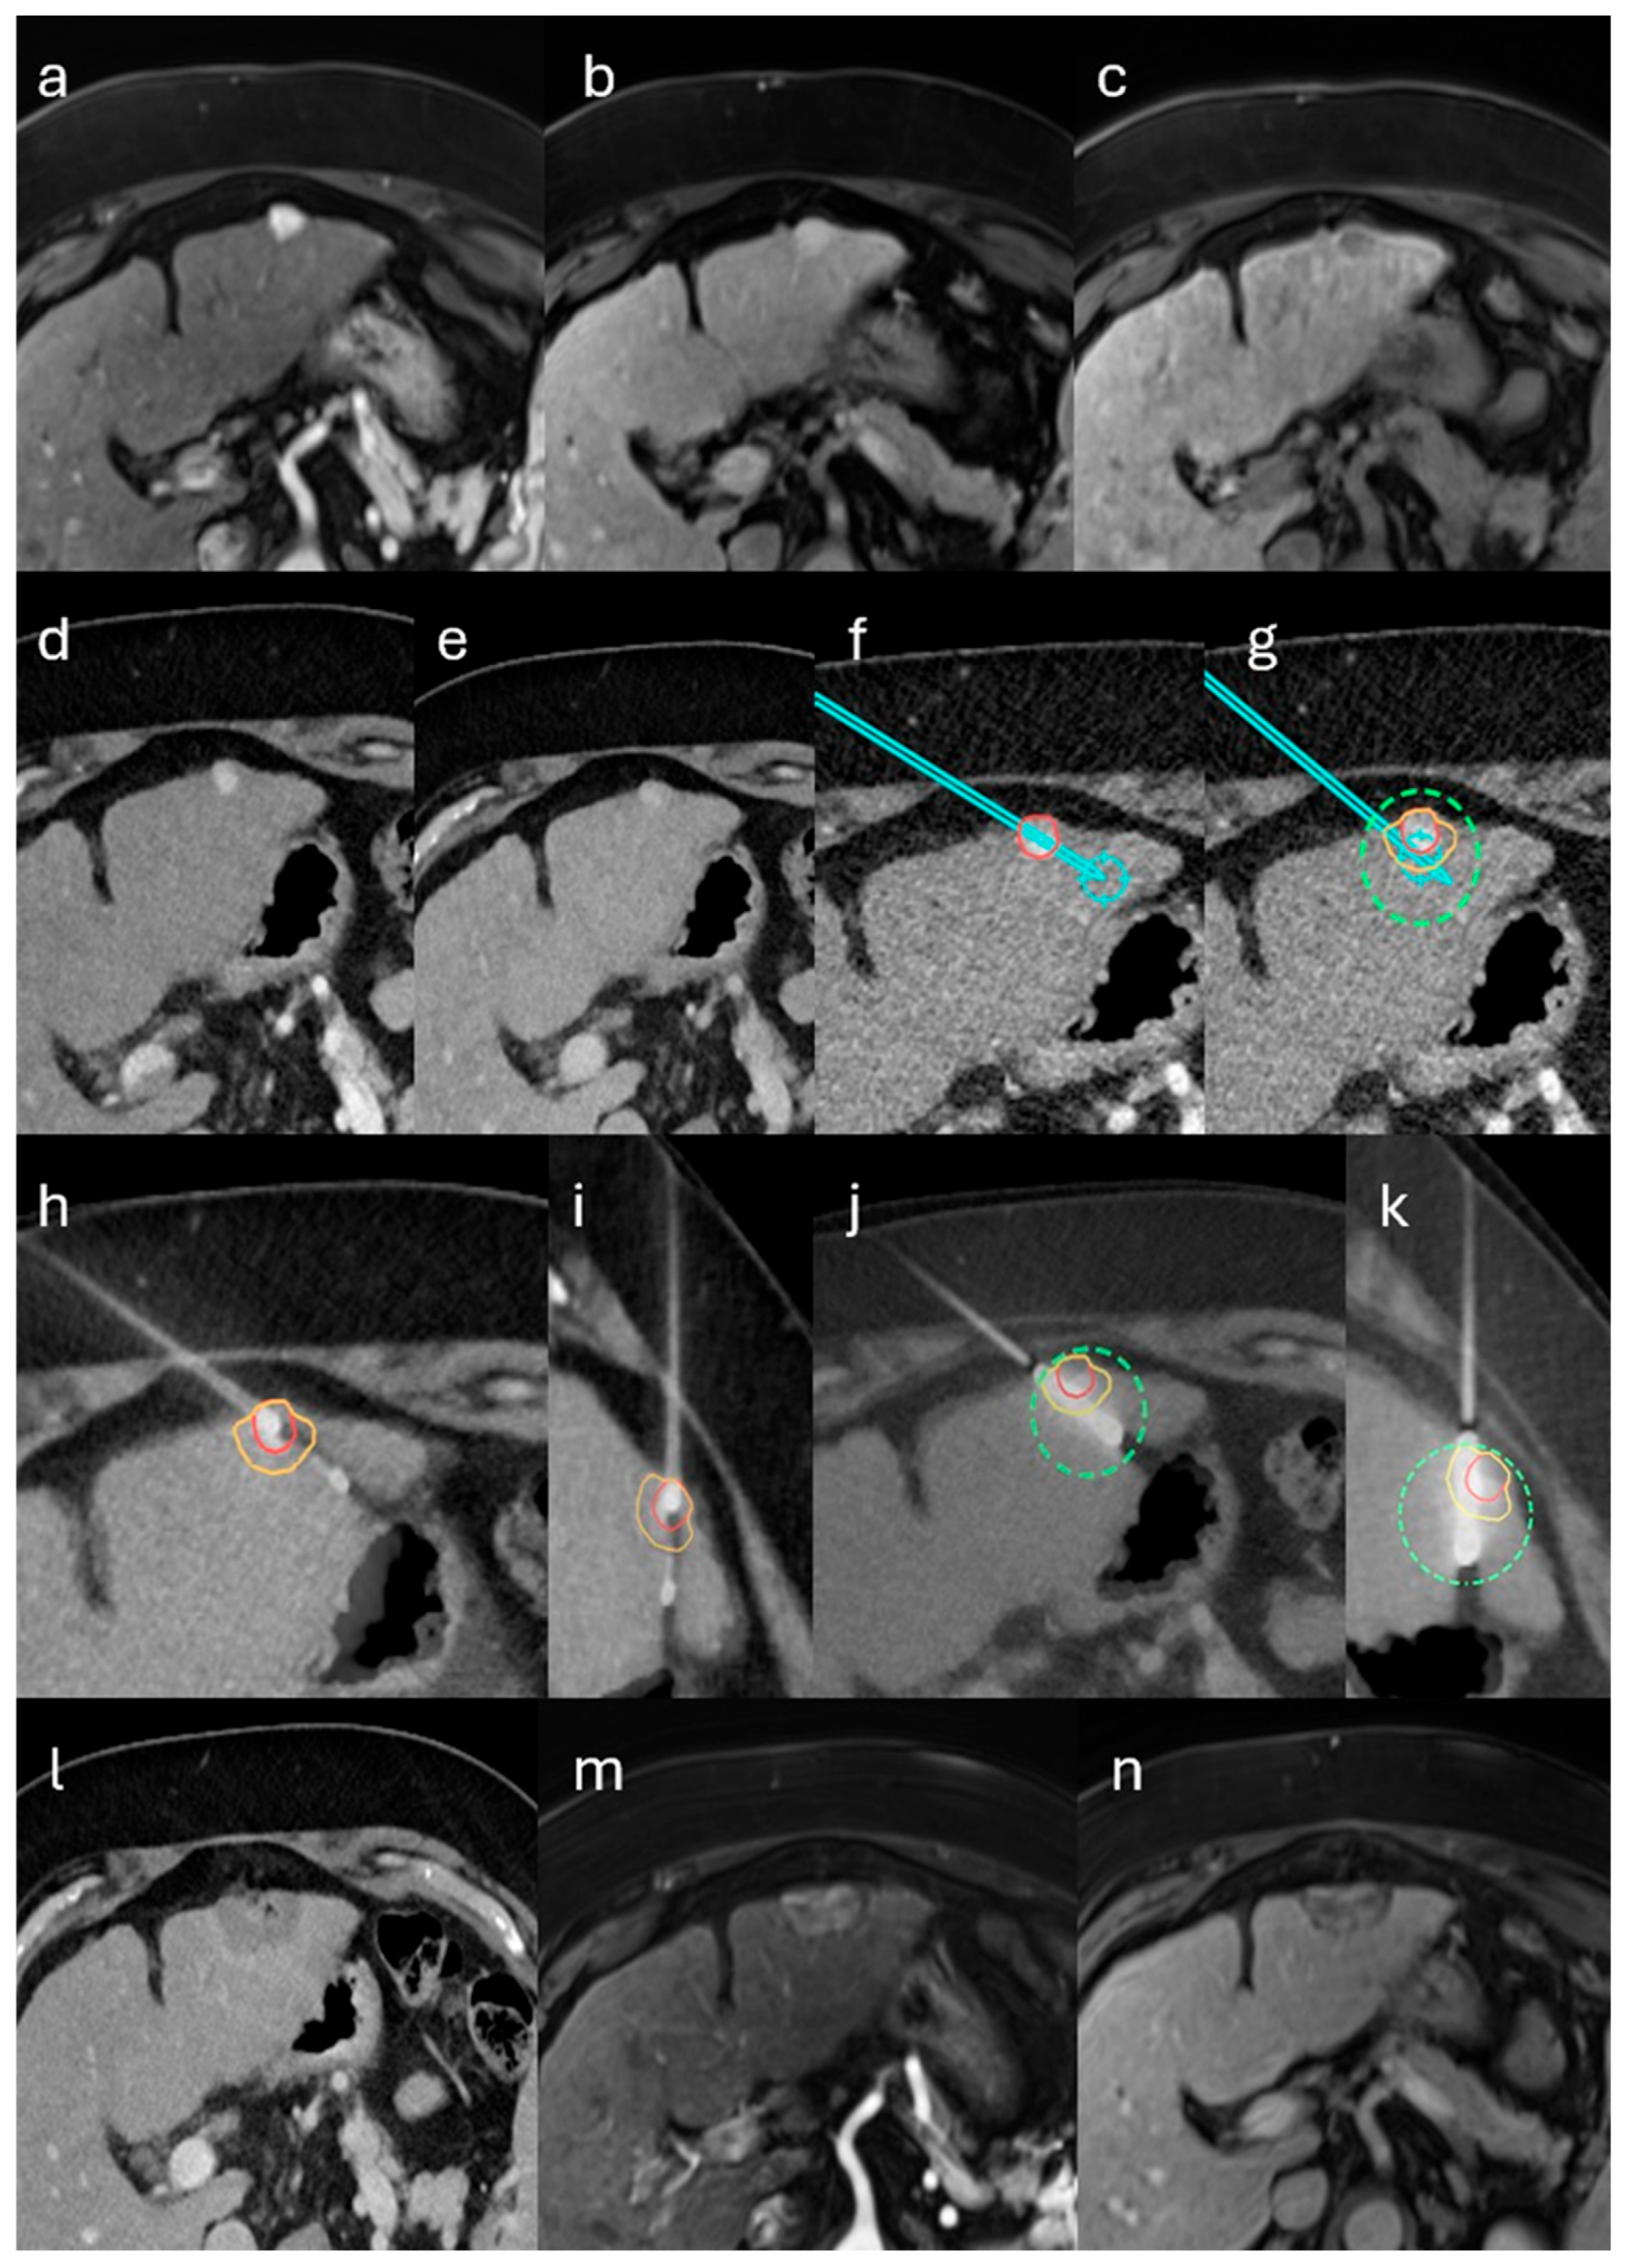

Per protocol, biopsy and ablation were performed consecutively during a single, uninterrupted anesthesia session. Definitive histology was available only after the procedure; intra-procedural pathology was not obtained, and the immediate ablation decision was not contingent on the biopsy result. Patients with predefined high-risk features were considered at increased risk of post-ablation abscess and, per protocol, would receive prophylactic antibiotics. High-risk features warranting prophylactic antibiotics were predefined as follows: bilioenteric anastomosis or recent biliary instrumentation (such as endoscopic retrograde cholangiopancreatography with sphincterotomy, biliary stent or drain, or pneumobilia). No patient in this cohort met high-risk criteria; therefore, prophylaxis was not administered. Antibiotics were initiated therapeutically only when post-procedural assessment suggested infection, such as compatible clinical signs with elevated C-reactive protein and/or leukocytosis. A representative case of the single-session workflow is illustrated in Figure 1.

Figure 1. Single-session stereotactic biopsy and microwave ablation (MWA) of an LI-RADS 4 lesion in the left hepatic lobe in a patient with alcoholic cirrhosis. (ac) Gadoxetate-enhanced MRI shows a 10-mm subcapsular lesion with non-rim arterial-phase hyperenhancement, no nonperipheral washout on the portal-venous phase, and hepatobiliary-phase hypointensity. Per LI-RADS v2018, major features yield LR-3; the hepatobiliary-phase hypointensity (ancillary feature favoring malignancy) upgrades the category to LR-4. (dg) Contrast-enhanced CT–based stereotactic planning with planned coaxial core-needle biopsy and MWA antenna trajectories and predicted ablation coverage including a 5-mm margin. (hk) Fused intraprocedural control CT confirms biopsy needle and antenna placement with expected coverage. (l) Immediate post-ablation CT demonstrates complete ablation; (m,n) 6-week MRI confirms sustained complete ablation. Histopathology demonstrated intrahepatic cholangiocarcinoma (CCA). Overlays denote the target lesion (red), planned biopsy and antenna trajectories (cyan path), the predicted ablation zone (green dashed outline), and the intended 5-mm safety margin (yellow or orange).